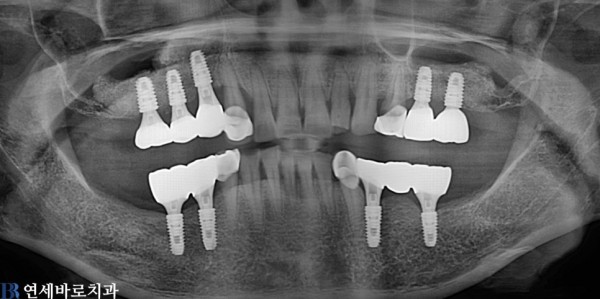

뼈이식과 상악동 거상술 임플란트 식립을 하여 총 임플란트 9개를 식립하였습니다.

환자분께서 너무 만족하셨고 치료가 잘 마무리 되었습니다.

구강외과전문의 원유진 대표원장님의 진료 사례입니다.

촬영시기: 22.08.10(전), 23.07.20(후)